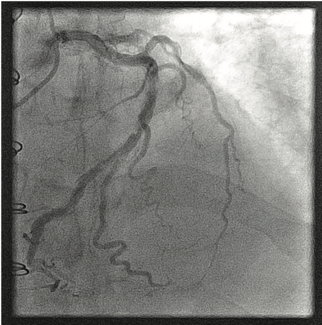

We describe a case of a right coronary artery (RCA) perforation that was successfully treated using a polyurethane-coated (PK Papyrus) stent (Biotronik).